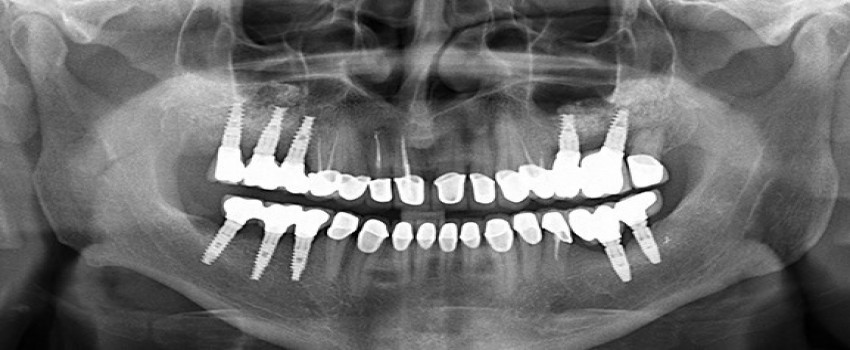

اگر شما فقط یک دندان از دست رفته دارید، فقط به یک ایمپلنت نیاز دارید. اگر دو یا چند دندان از دست رفته دارید ممکن است برای هر دندان، یک ایمپلنت احتیاج نداشته باشید، تعداد کاشت مورد نیاز با توجه به حجم استخوان در محلی که قرار است ایمپلنت گذاشته شود تعیین می شود. در فک فوقانی، حجم استخوان به طور کلی ضعیف تر است، بنابراین معمولاً کاشت دندان بیشتر از قوس پایین مورد نیاز است. در فک پایین معمولاً چگالی استخوان وجود دارد، بنابراین کمتر به کاشت بالاتر از قوس فوقانی نیاز است.

شکاف سه دندان از دست رفته در هر نقطه از دهان به طور معمول منجر به دو ایمپلنت دندان می شود که از سه دندان پشتیبانی می کنند.

شکاف چهار دندان از دست رفته در جلوی دهان به طور معمول منجر به دو ایمپلنت دندان می شود که از چهار دندان پشتیبانی می کنند.

شکاف چهار دندان از دست رفته در پشت دهان به طور معمول منجر به سه ایمپلنت دندانی می شود که از چهار دندان پشتیبانی می کند.

اگر شما همه ی دندان های خود در یک فک یا هر دو فک را از دست داده اید، میزان کاشت دندان مورد نیاز برای قوس کامل دندان ها به چند عامل بستگی دارد: